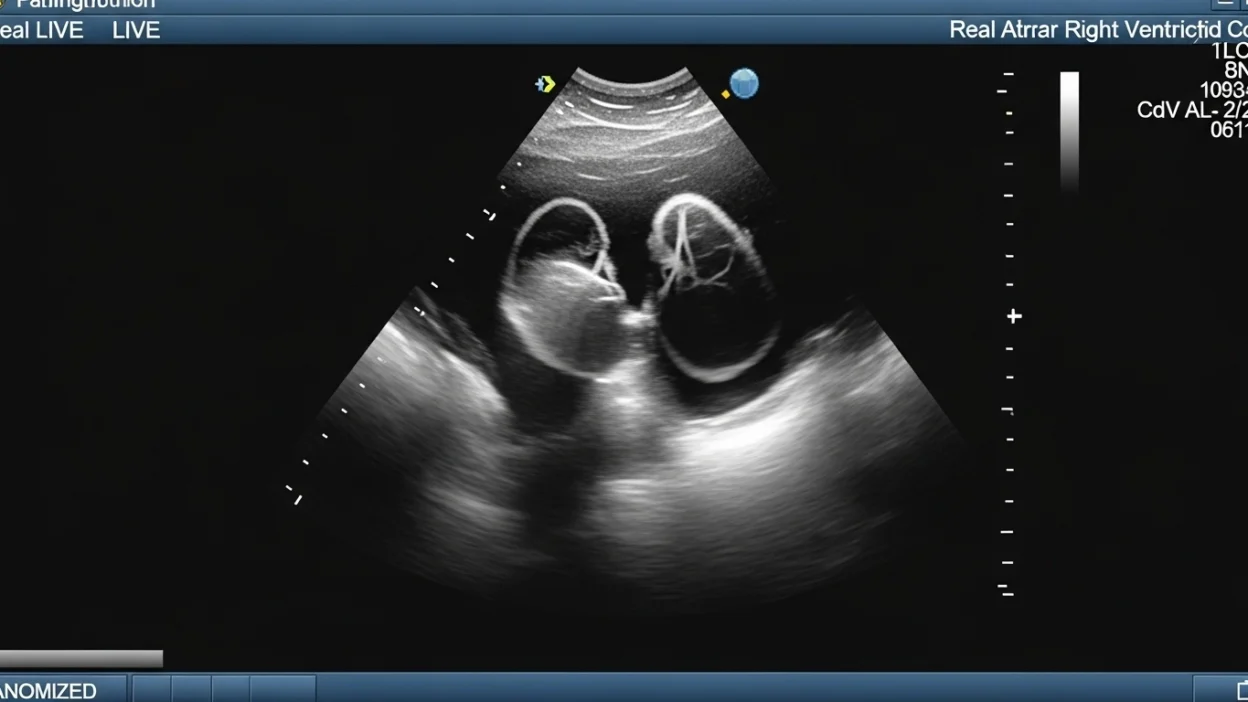

An echocardiogram is a medical imaging test that uses ultrasound waves to create moving pictures of the heart. The test allows doctors to examine the heart’s structure and function in real-time, providing essential information about how well the heart is working.

During an echocardiogram, a small device called a transducer sends sound waves into the chest. These waves bounce off the heart structures and return as echoes, which are converted into detailed images on a monitor. This allows doctors to visualize the size and thickness of heart chambers, the motion of the heart walls, and the function of the heart valves. Advanced techniques, such as Doppler echocardiography, can also measure the direction and speed of blood flow, helping identify conditions like valve disorders or blood clots.